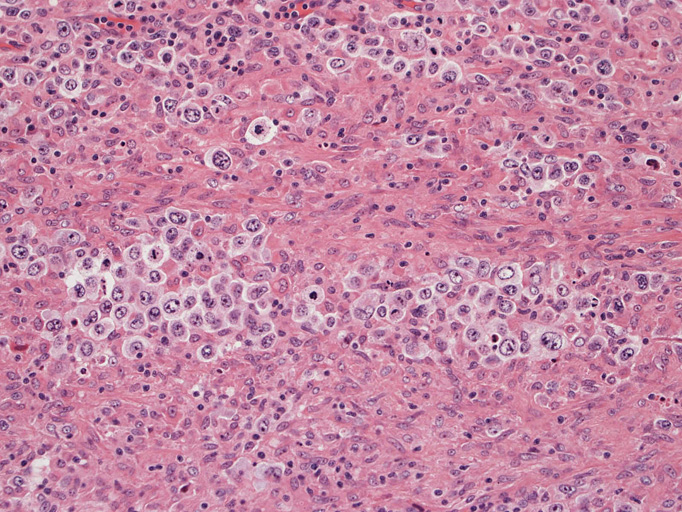

結節構造内では, 好酸性細胞質をもつ組織球の増生を背景に大型異型細胞が散在性または集蔟して増殖している。被膜下にも線維化組織内にbizzarreな大型細胞が認められる。リンパ球は小型リンパ球が大型異型細胞を含む組織球性の結節辺縁に存在する。大型細胞は, centroblastic cellが多く, その他 Hodgkin cell-like cell, RS細胞様巨細胞, 腎臓型の核をもった細胞, 多型核の細胞など多彩な形態を示す。異型核分裂像をふくむ核分裂像が多い。

大型異型細胞の形態